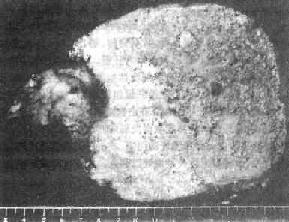

病变绝大多数泡状棘球囊肿见于肝,一般呈单个巨块型,有时为结节型,或两者兼有。泡球蚴囊泡常呈灰白色,质较硬,由无数小囊泡集合而成海绵状,与周围组织分界不清(图19-19)。囊泡内容物为豆腐渣样蚴体碎屑和小泡。陈旧病灶的中央因营养不佳常发生变性、坏死,或溶解呈胶冻状液体。如继发感染,可酷似脓肿。泡状囊肿外周无纤维包膜,向外芽生性子囊可以像癌肿一样向周围组织浸润,并可侵入血管或淋巴管,转移到肺、脑、脾、肾、肾上腺及心脏等处,甚至偶然可见于肝门淋巴结内,因此肉眼上易误诊为肝癌。镜下,在肝组织中散在大小不等的泡状蚴小囊泡,一般仅见角皮层,偶尔有单细胞性生发层,偶见原头蚴。囊泡周围有嗜酸性粒细胞浸润,伴有结核样肉芽组织形成及纤维组织增生。囊泡间的肝组织常发生凝固性坏死(图19-20)。病变周围肝组织常有肝细胞萎缩、变性或坏死及淤胆现象。最后可导致肝硬变、黄疸、门静脉高压和肝功能衰竭及恶病质。

图19-19 肝泡状棘球蚴病(巨块型)

切面上见由无数小囊泡集合而成